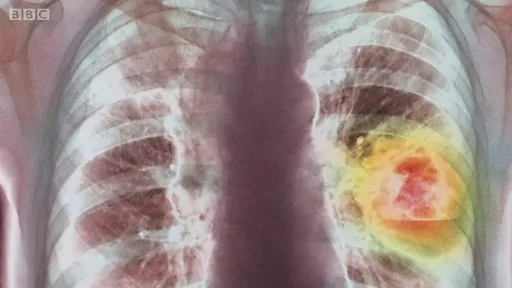

Des organes transplantés causent un cancer

Plus tard, on a découvert une petite tumeur cancéreuse dans l'organe du donneur qui n'a pas été détectée par le dépistage avant la transplantation.

Mais "dans de très rares cas, il est possible que le donneur ait une petite tumeur qui ne peut pas être détectée par les tests effectués dans le temps limité disponible avant la transplantation".

"Cela signifie que la transmission d'un cancer non diagnostiqué est un risque, mais heureusement, c'est extrêmement rare".